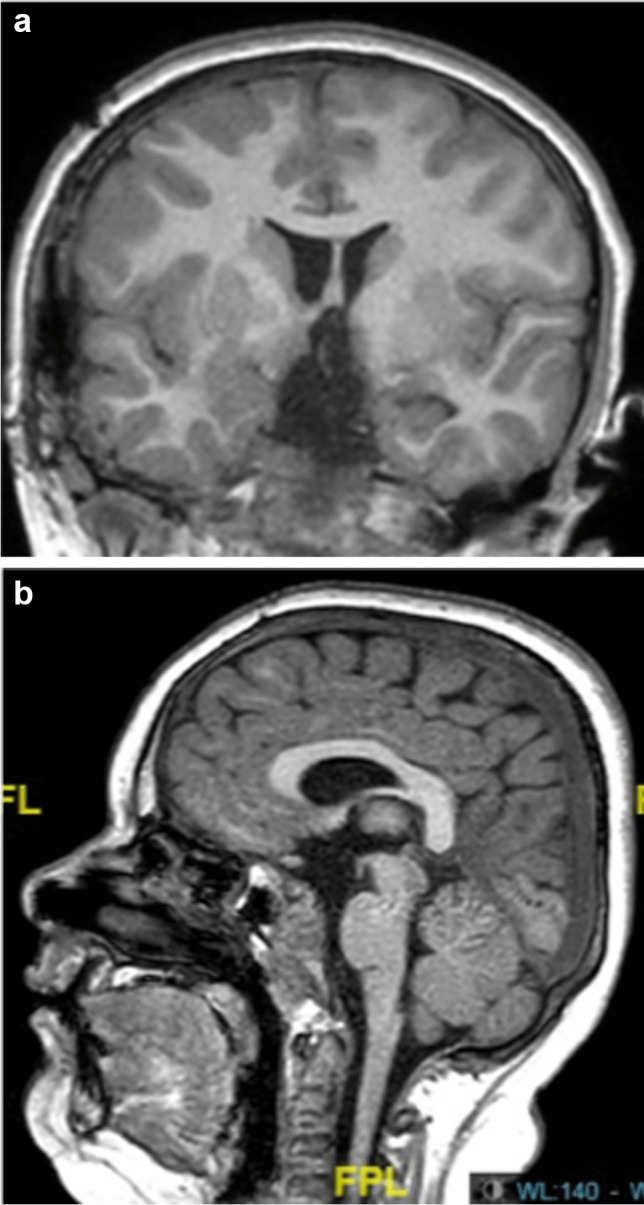

Background: Craniopharyngioma (CP) surgery in children leads to high rate of recurrence, and morbid complications. Transcranial approach is the most frequently proposed surgical technique, but transsphenoidal endoscopic approach is also used. Pre- and post-operative complications of the tumor are well known, but early multidisciplinary management could improve the long-term outcome of these patients. The aim of this study was to analyse the risk factors for pre-and post-operative long-term complications in a series of patients operated with an aggressive removal for CP.

Methods: A retrospective study of 26 children diagnosed with CP was carried out. The surgical total removal was possible in 88% of cases after the revision of the post-operative MRI realized in the first 48 h.

Results: Children with hypothalamic involvement were more likely to have endocrine deficits and to be overweight or obese pre-operatively. They also had a higher risk of early post-operative complications, and late morbidities.

Conclusion: Children with CP and strong hypothalamic involvement, have a higher risk of pre- and post-operative complications but complete removal is associated with a high rate of cure with global good neuropsychological results. Early multidisciplinary post-operative management should be reinforced to improve the long-term outcome but surgery with total removal can insure definitive acceptable clinical results.